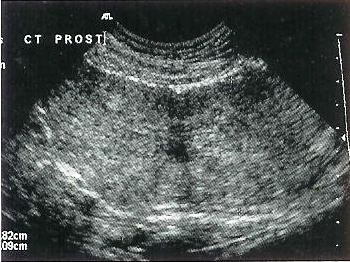

Glandulär-zystische Hyperplasie

Diese Erkrankung der Gebärmutter hängt mit einer übermässigen Reaktion der Gebärmutterschleimhaut (Endometrium) auf die Stimulation durch das Hormon Progesteron zusammen. Das Endometrium besitzt zahlreiche kleine Drüsen, die sich übermässig stark verdicken können, zystös werden und schliesslich zu einer Verdickung der gesamten Gebärmutterwand mit Verlust ihrer Elastizität führen. Dadurch werden die Embryonen an der Einnistung in der abnorm veränderten Gebärmutterschleimhaut gehindert. In einigen Fällen ist diese Anomalie bei der Ultraschalluntersuchung der Gebärmutter zu erkennen. Gelingt dies nicht, muss eine Gewebeprobe auf chirurgischem Weg entnommen werden (Biopsie).

Die glandulär-zystische Hyperplasie der Gebärmutter ist in vielen Fällen irreversibel. Einige hormonelle Behandlungen (Anti-Progesteron, nur in einigen Ländern erhältlich) haben sich gelegentlich als wirksam erwiesen. Ohne erfolgreiche Therapie wird sie oftmals durch eine sehr schwere Erkrankung kompliziert - die Pyometra (eitrige Gebärmutterentzündung). Nach mehreren hintereinander folgenden Läufigkeiten kommt es zu einer immer hochgradigeren Veränderung des Endometriums. Die Ursache einer Pyometra ist eine Ansammlung von Sekreten in der Gebärmutter, die schliesslich mit Bakterien kontaminiert wird.

Links: Typisches Erscheinungsbild einer Gebärmutter mit glandulär-zystischer Hyperplasie nach chirurgischer Kastration. Ohne Behandlung entwickelt sich diese Erkrankung zu einer Pyometra, die das Leben der Hündin gefährden kann.

Rechts: Ultraschall ist das Untersuchungsverfahren der Wahl für die Diagnose der glandulär zystischen Hyperplasie.